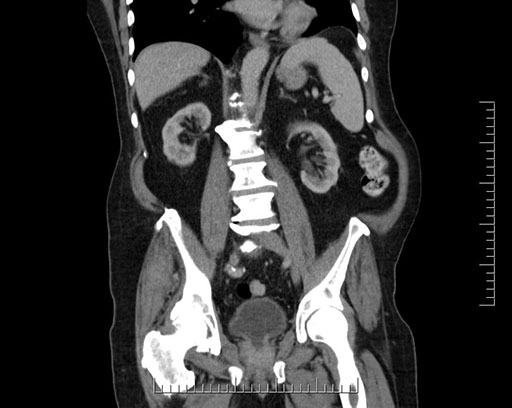

Coronal - stented